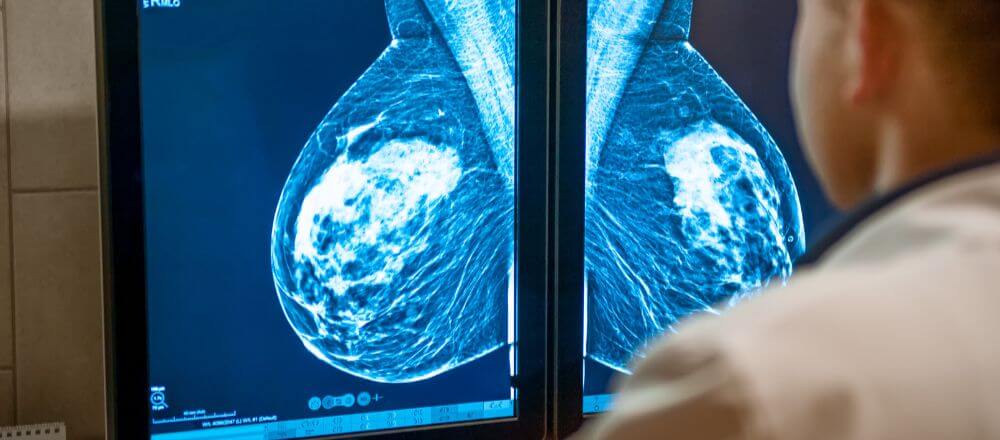

การตรวจแมมโมแกรม (Mammogram) คือ การเอกซเรย์เต้านมโดยใช้รังสีพลังงานต่ำถ่ายภาพเต้านมด้านละ 2 รูป เพื่อวินิจฉัยหาความผิดปกติของเต้านมตั้งแต่ในระยะเริ่มแรก คล้ายกับการเอกซเรย์ทั่วไปแต่ใช้ปริมาณรังสีน้อยกว่า 30-60% โดยภาพถ่ายที่ได้จากการตรวจแมมโมแกรมจะมีความละเอียดสูง ทำให้มองเห็นจุดผิดปกติได้แม่นยำแม้จะมีขนาดเล็ก

• ภาพแมมโมแกรมคมชัด ทำให้แพทย์ตรวจพบจุดผิดปกติได้ดีแม้จะมีขนาดเล็กมาก

รอยโรคมะเร็งเต้านมมีขนาดเล็กมาก ทำให้ในระยะแรกเริ่มมักไม่มีอาการหรือความผิดปกติใด ๆ ดังนั้น นอกจากการตรวจเต้านมด้วยตัวเองเป็นประจำแล้ว การตรวจแมมโมแกรมก็เป็นอีกหนึ่งวิธีคัดกรองมะเร็งเต้านมที่ดีที่สุด สามารถตรวจพบลักษณะผิดปกติในเต้านม เช่น ก้อนน้ำ ก้อนเนื้อ หรือจุดหินปูน รวมทั้งรอยโรคที่มีขนาดเล็กได้ ซึ่งการตรวจพบความผิดปกติได้ตั้งแต่เนิ่น ๆ นั้น หากตรวจแล้วทำการรักษาทันทีก็มีโอกาสหายขาดได้เกือบ 100% ลดอัตราการเสียชีวิตจากการเป็นมะเร็งเต้านมได้